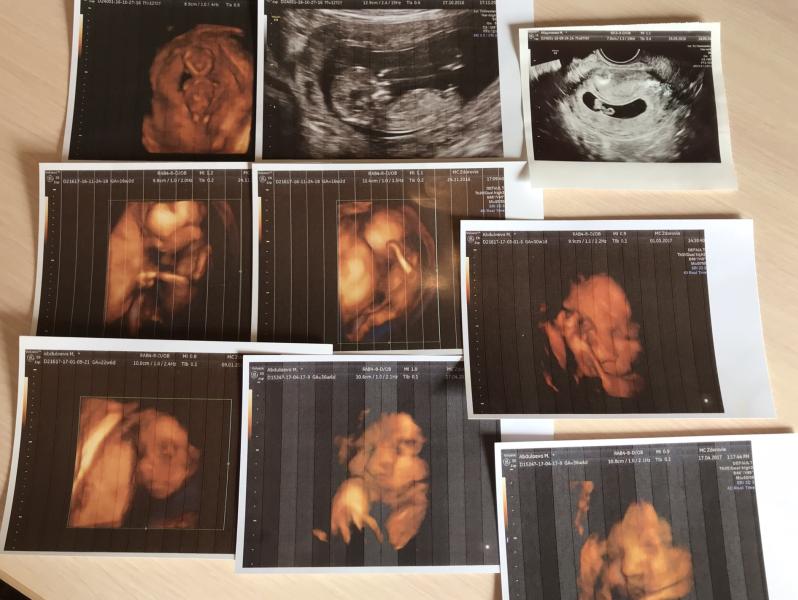

2 сентября 2016 год... второй день задержки. Проснулась в 9 утра и со страхом пошла в ванную, но Альх’амдулиЛлагь месячные не пошли. Поехали с мужем в аптеку, купила эвитест. Муж привез меня домой, а сам поехал на Джума. Я не помню как поднялась на 4 этаж и сразу же побежала ставить тест, Через пол минуты уже начала виднеться вторая полоска😍Альх’амдулиЛлагь спустя год и месяц планирования она наконец появилась. Просто сидела и плакала держа в руках тест😀пришёл муж, увидев меня говорит: он же дол...